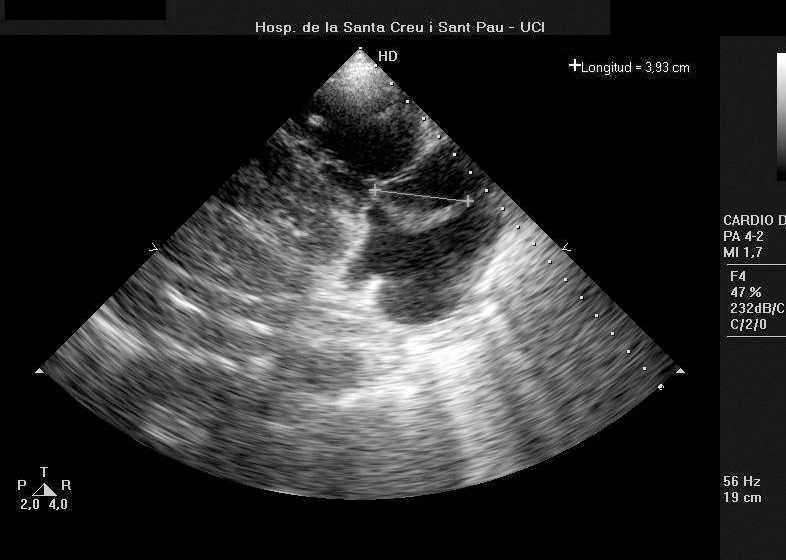

En pocos días presenta nuevo deterioro con shock séptico a pesar del tratamiento antibiótico. Aparece soplo tricuspídeo 4/6, por lo que se realiza ecocardiografía transtorácica en la que se objetiva la existencia de vegetación tricúspide voluminosa (4,5 cm en su diámetro longitudinal) en la valva septal con insuficiencia de moderada a importante.

Figura 1. Imagen ecográfica de la vegetación sobre la válvulatricúspide de 3,93 cm de tamaño.

Las características ecográficas3, un gran tamaño (hasta 3,5 cm en las EF frente a menos de 1 cm de las bacterianas), ratificarían el diagnóstico.